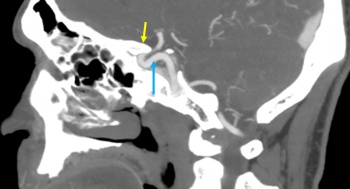

CTA/MRA: CTA and MRA are often used as first-line noninvasive imaging modalities to evaluate CCFs (Figure 4).[31] CTA and MRA will identify the majority of arterial dissections and cavernous ICA aneurysms causing a CCF as well as enlargement of the affected CS. These modalities can also detect abnormal flow voids, proptosis, enlargement of the SOV/IOV and enlargement of extraocular muscles.[32]

CT: CT without contrast is a useful screening modality to detect skull base fractures in the setting of trauma. Performed with contrast without CTA, a CT may reveal proptosis and engorgement of the SOV.

MRI: Compared to CT, MRI can better demonstrate fat stranding reflecting orbital edema and abnormal flow voids.[33]

Although non-invasive studies can demonstrate findings suggestive of CCF, they cannot definitively diagnosis a CCF which requires the presence of abnormal venous drainage due to the fistulous connection. Further, the absence of findings on non-invasive imaging does not exclude a diagnosis of CCF.